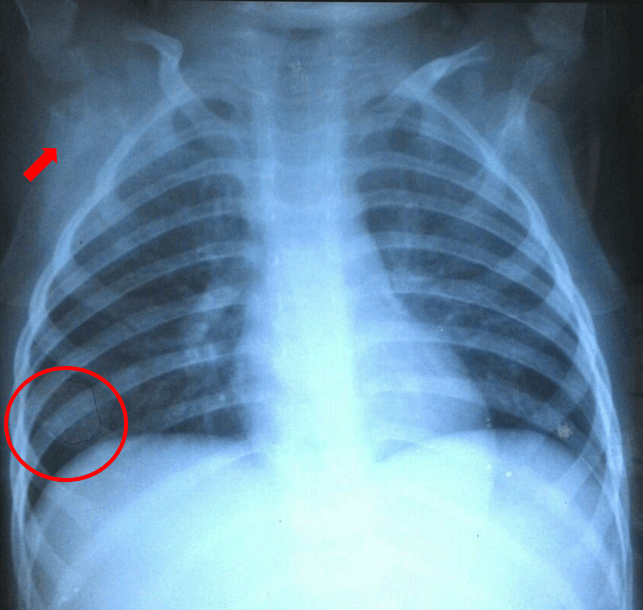

Chest X-ray revealed a solitary nodule on the right paracardial region suspicious for metastasis of pulmonary nodular type (differential diagnosis: primary mass) and the destruction of the right scapular bone very likely the process of metastasis (Figure 2). Head computed tomography (CT) scan revealed soft tissue masses on left frontoparietal and left parietooccipital region with administration of contrast showed enhancement. The masses looked destructed bone underneath that seems to infiltrate the brain parenchyma (Figure 3).

Figure 2: Chest X-ray showing solitary nodule (red circle) and right scapular bone destruction (red arrow).